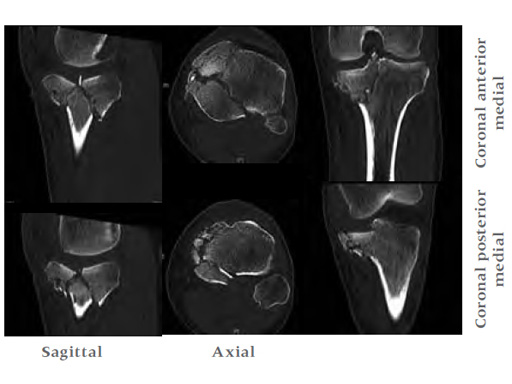

A 33-year-old male was involved in an altercation and suffered a gun shoot wound to his knee

Case provided by Brent Norris, Tulsa, USA.

Initially taken for incision and drainage and then ORIF . Patient placed in a floppy lateral position with the effected lower extremity externally rotated (opposite hip and shoulder bumped up about 3040) allowing exposure of the posterior medial knee. A posterior medial and an anteromedial incision were used to repair the fracture with a 67 cm skin bridge.

Postoperative healing was uneventful and the patient had no complications.